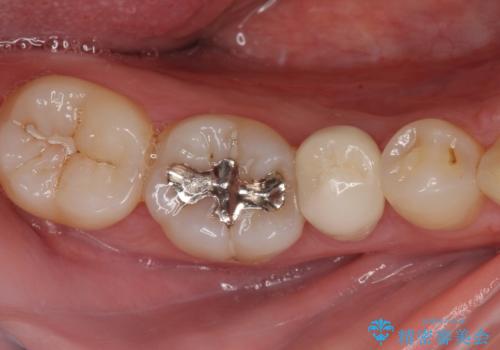

銀歯を白くして見た目を改善したい !

もげてしまった奥歯 オールセラミッククラウンでの補綴治療